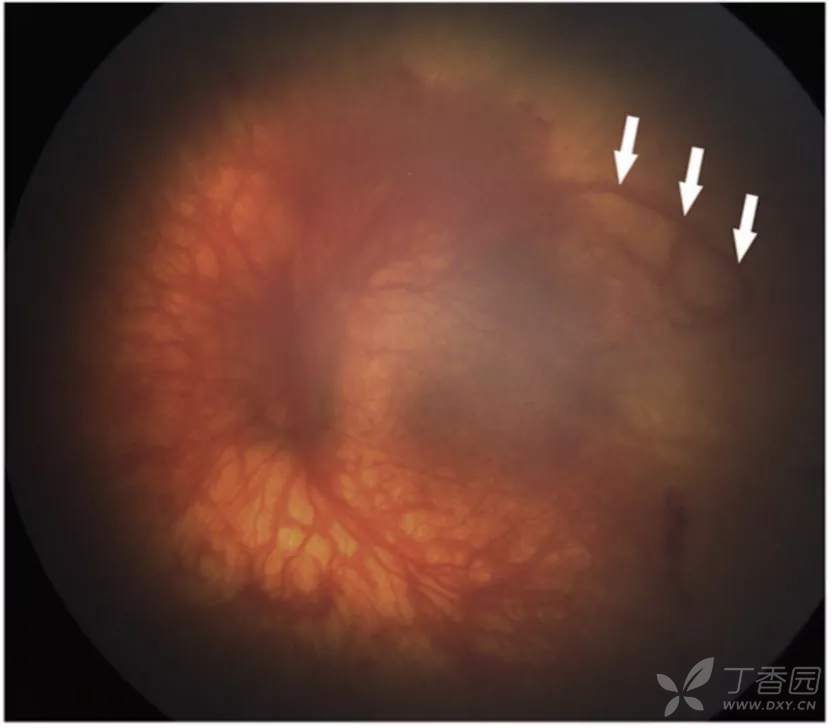

图. I区视网膜血管区和无血管区边界可见扩张的血管袢(白箭),弥漫性平坦的视网膜外新生血管,颞上方最为明显,伴严重plus病变。